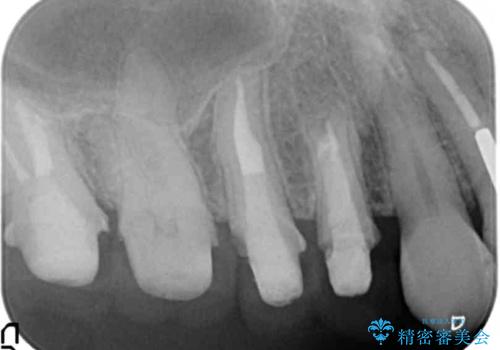

臼歯部メタルフリー再補綴

- 治療してからの年月が経過し、かみにくくなったブリッジ・クラウンを全てやりかえたいと希望され来院されました。

クラウン・ブリッジを作り替えるにあたり虫歯の徹底的な除去・根管治療のやり直しを行い今後やり直しをしなくて済むような環境を整えていきます。

装着して長期間経過したブリッジやクラウンは隙間から細菌が侵入し虫歯が再発してしまっていることがあります。

長期的に問題のないブリッジ・クラウンを作製するため、虫歯をしっかりと除去すること精密な根管治療を行うことが肝要です。